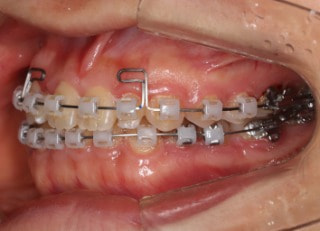

治療開始時

治療開始から25ヶ月後